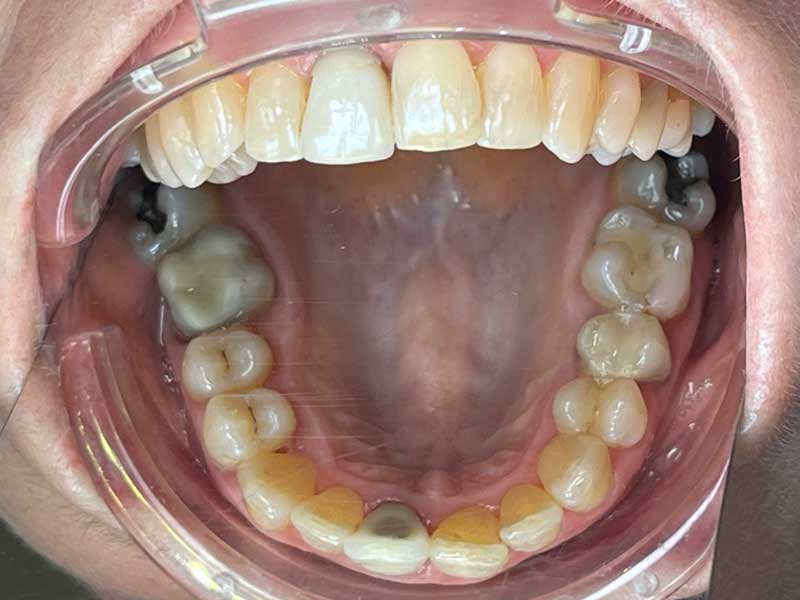

Situation initiale · Octobre 2022

La photo initiale révèle une situation clinique sévère, caractéristique d'une malocclusion adulte non traitée sur plusieurs décennies :

Les deux arcades présentent un désalignement important, avec des rotations multiples et des chevauchements marqués sur les deux mâchoires

Plusieurs restaurations prothétiques existantes — couronnes ou éléments prothétiques — indiquent des soins dentaires au fil des années, sans que la composante orthodontique n'ait jamais été abordée

Les gencives présentent une inflammation visible, directement liée à la difficulté d'hygiène dans un contexte d'encombrement aussi marqué

Les deux arcades présentent des problématiques différentes en nature et en intensité — ce qui a guidé le choix d'un protocole asymétrique